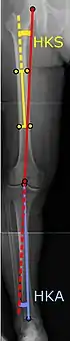

Para indicar el reemplazo de rodilla en caso de osteoartritis, su clasificación radiográfica y la gravedad de los síntomas deben ser sustanciales. Dicha radiografía debe consistir en radiografías en carga de ambas rodillas: AP, lateral y 30 grados de flexión. Es posible que las proyecciones AP y lateral no muestren un estrechamiento del espacio articular, pero la vista en flexión de 30 grados es más sensible al estrechamiento. También se utilizan proyecciones de longitud completa para ajustar la prótesis para proporcionar un ángulo neutro para la extremidad inferior distal. Dos ángulos utilizados para este propósito son:

- Ángulo cadera-rodilla-eje (CRE),[8] un ángulo formado entre una línea que pasa por el eje longitudinal de la diáfisis femoral y su eje mecánico, que es una línea desde el centro de la cabeza femoral hasta la muesca intercondilar de la diáfisis femoral. fémur.[10]

- Ángulo cadera-rodilla-tobillo (CRT),[9] que es un ángulo entre el eje mecánico femoral y el centro de la articulación del tobillo.[10] Normalmente se encuentra entre 1.0° y 1.5° de varo en adultos.[11]

CRT: Ángulo cadera-rodilla-tobillo, que idealmente está entre 3° en varum y 3° en valgum desde un ángulo recto.[54]